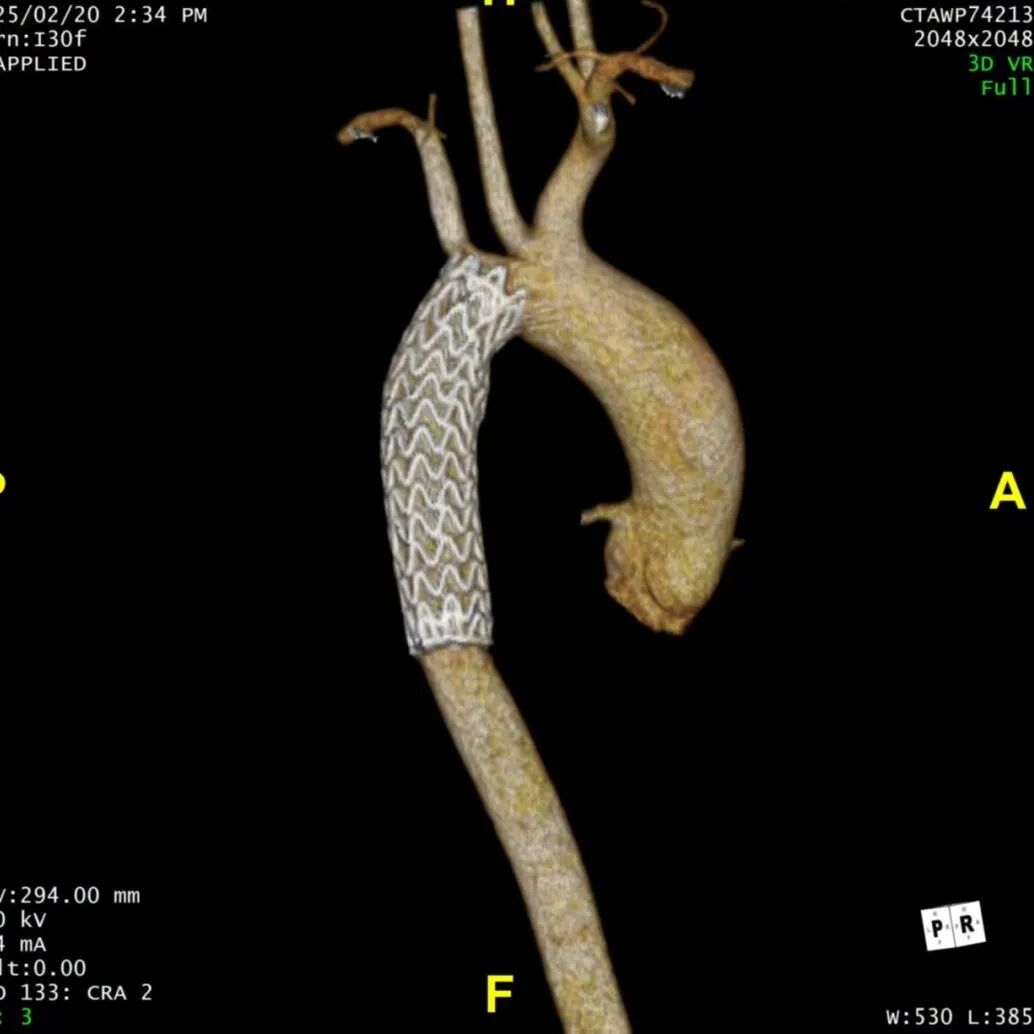

患者在半年后进行随访,支架形态良好,夹层隔绝完全。

术后复查CTA

术后3D重建